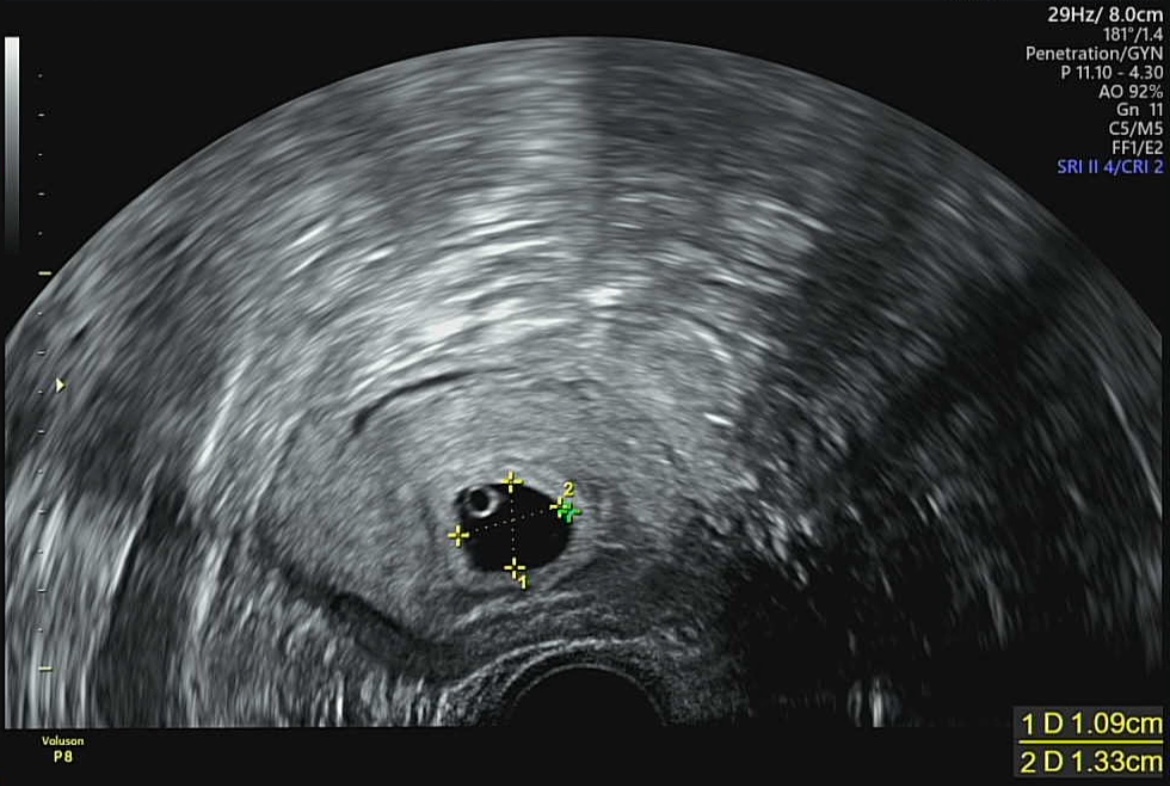

난황을 확인할 수 있는 시기는 보통 4~6주차로 이르면 4주차에도 확인 가능합니다. 저 같은 경우에는 5주차 6일에 난황과 아기집을 동시에 확인했습니다. 이런 난황의 위치로도 성별을 확인할 수 있다고 합니다. 아래 사진과 같이 왼쪽 위, 아래에 있다면 아들! 오른쪽 위, 아래에 있다면 딸을 의미합니다. 하지만, 초음파기계별로 세팅이 다르기 때문에 좌우반전이 있을 수도 있다는 점을 참고하시기 바랍니다. 현재 보이는 초음파 사진상으로는 아들의 위치에 난황이 있었는데, 아무래도 좌우반전이 있던 초음파였을지도 모른다는 추측입니다.